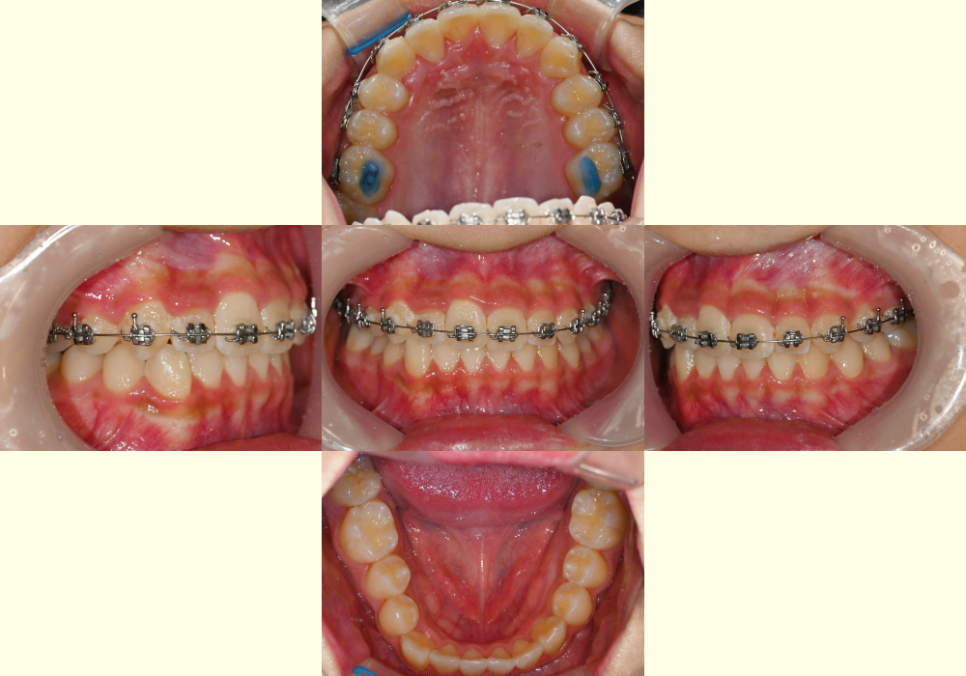

구강 내 모습을 보면

위아래 치열이 삐뚤빼뚤하며

윗니가 아랫니의 1/2~2/3 이상

덮어있는 과개교합(deep bite)으로

보였습니다.

더불어, 치아 사이 치석과 구강 위생 상태가

좋지 않아 본격적인 교정 전 스케일링과

구강 관리 교육을 우선 시행이 필요해 보였습니다.

23.12.14

앞서 계획한 것과 같이 브라켓을 부착한 뒤

서서히 자연치가 이동할 수 있도록

지속적인 진료를 진행합니다.

이때, 위턱 양쪽 어금니에

바이트 블록을 쌓아 교합을 올려준 뒤

이를 이동시킵니다.